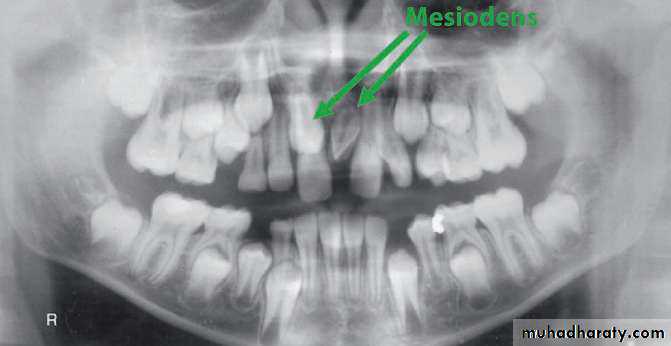

• Mesiodens :When they occur between the maxillary central incisors.

Parateeth(paramolar): Those occurring in the molar area .

Distodens or distomolar : Those that erupt distal to the third

molar.

Paramolar blocking the eruption of 3rd molar.

MesiodensDistomolars(4th molar)

Mesiodens

Distodens or distomolarParamolar